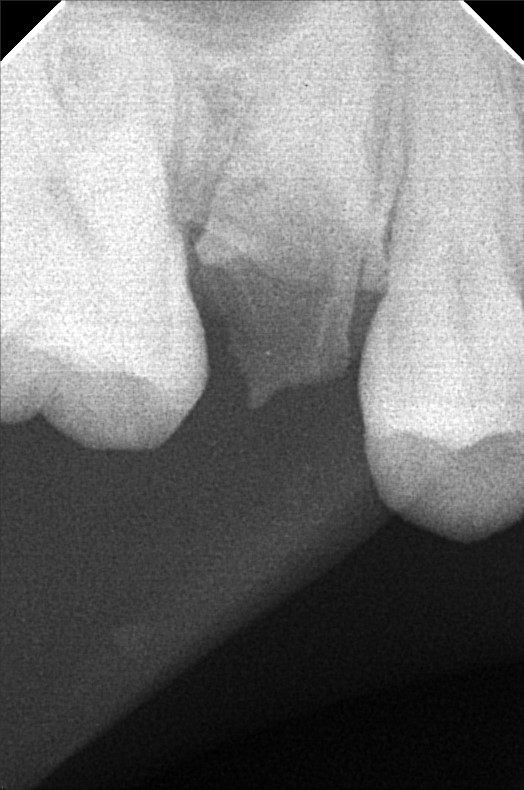

Edit Record Check our patient data records. Add patient information Patient Info Profile picture Last Name First Name Middle Name Birthdate Age Street Barangay City Country Zip Code Contact number Email Procedure 06/30/23- Informed Consent Ortho Check Up OP Impression Soft tissue analysis Intraoral photograph PA Radiograph For exo #15 Informed pt regarding class 5 cases Referred for cephalometric radiograph For resto class 5 #23, #24, #25, #35, #13, #14 10/24/25 oral prophylaxis xray tooth extraction #15 for restoration: abrasion: #23, 24, 25, 26, 14, 33, 35, 36, 44 recession: #13, 12, 11, 21, 22, 34, 32, 43 File atecotech2i712f_f.jpeg File 2 atecotech2i18f6_f.jpeg File 3 atecotech2i2a08_f.jpeg File 4 atecotech2i6330_f.jpeg File 5 atecotech2i278f_f.jpeg File 6 atecotech2i5dba_f.jpeg File 7 File 8 File 9 File 10 File 11 File 12 File 13 File 14 File 15 File 16 File 17 File 18 File 19 File 20 Retain Record Retain Record Yes No Save Your Changes